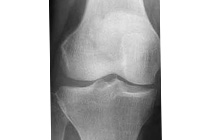

A) 変形性ひざ関節症の病態に関しては5月号で既に述べました。ひざを構成する3つの骨、大腿骨(太ももの骨)、脛骨(すねの骨)、膝蓋骨(お皿の骨)はいずれも、表面が軟骨というクッションに覆われています。大腿骨と脛骨の軟骨間には、さらに半月板という軟骨のクッションが挟まれた構造になっています。加齢によって軟骨が変性し、摩耗し始めると、歩き過ぎなど何らかの負担がかかった際に、ささくれだった軟骨が剥がれ落ちます。その破片が刺激となって関節の袋の内側の滑膜(かつまく)という組織が炎症を起こし、滑液(かつえき)が分泌され、関節内に溜まります。これが腫れや痛みなどの症状を引き起こします。